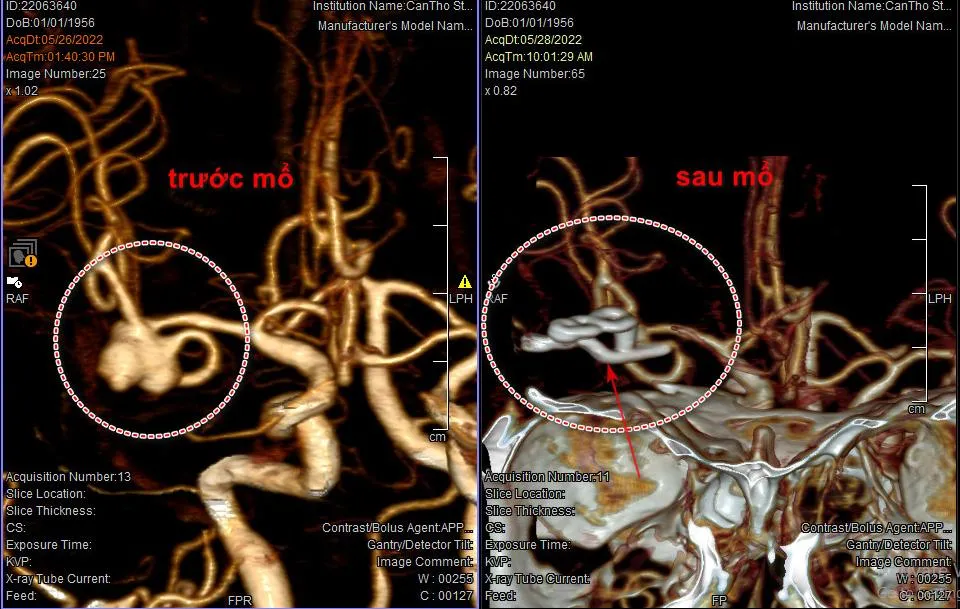

Hình ảnh chụp CT cho thấy bà V. bị vỡ mạch máu não trước và sau điều trị. Ảnh: BVCC |

Tại đây, sau khi chụp CT, các BS chẩn đoán bà V. bị xuất huyết khoang dưới nhện do vỡ phình mạch máu.

Các BS nhanh chóng phẫu thuật kẹp cổ túi phình cầm máu, đồng thời lấy máu tụ đã chảy chung quanh túi phình.